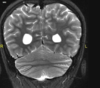

4

Q

A

Esclerose mesial temporal

Observe a perda de volume, que indica atrofia e causa aumento secundário do corno temporal do ventrículo lateral.

O sinal alto no hipocampo reflete a gliose.

How well did you know this?

Qual o padrão da Esclerose mesial temporal?

Atrofia hipocampal e hipersinal T2. Cerca de 10% dos casos são bilaterais (dificulta o diagnóstico). A etiologia é desconhecida, mas há uma relação entre STM e convulsões febris prolongadas no início da vida A esclerose mesial temporal pode ocorrer em associação com outras patologias, principalmente displasia cortical focal (dual pathology).